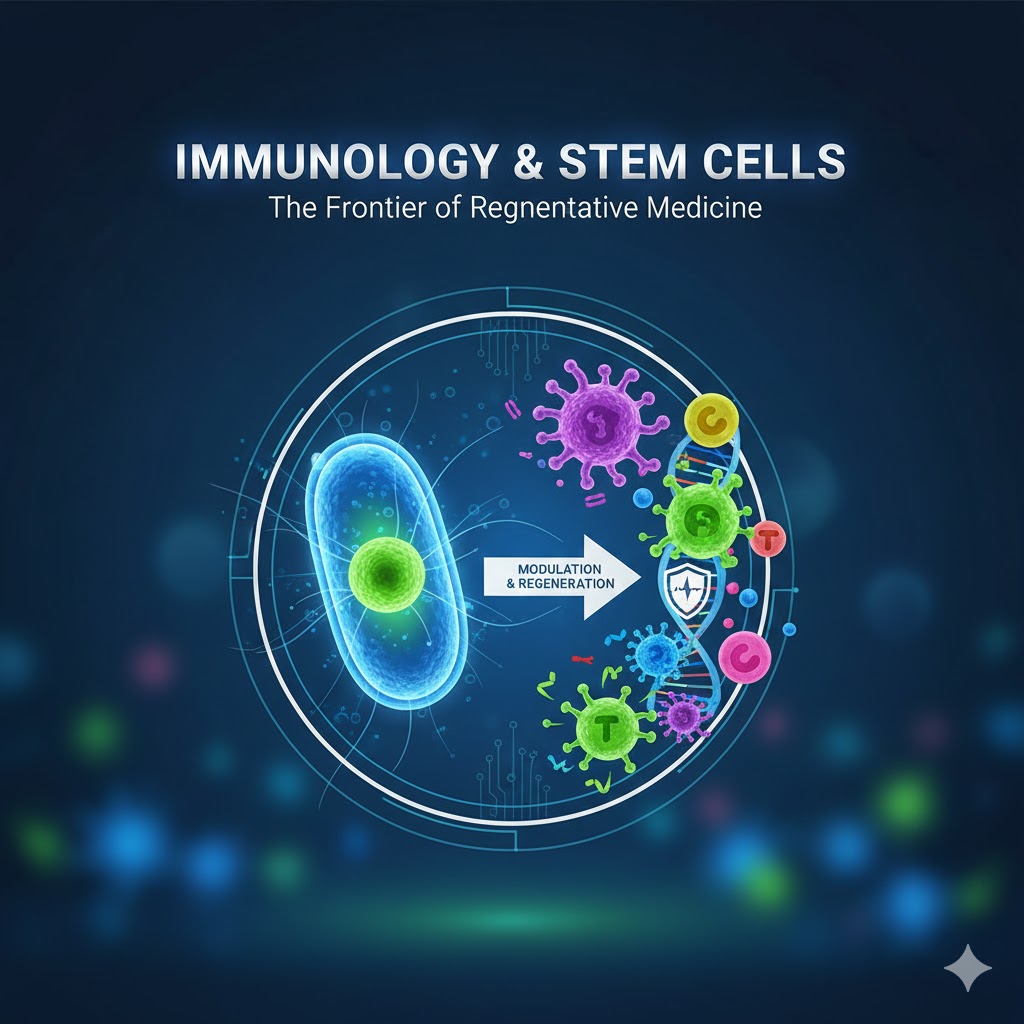

Các phác đồ được xây dựng dựa trên báo cáo khoa học

Đội ngũ có kinh nghiệm trong tế bào gốc, miễn dịch học, công nghệ sinh học, y học phân tử